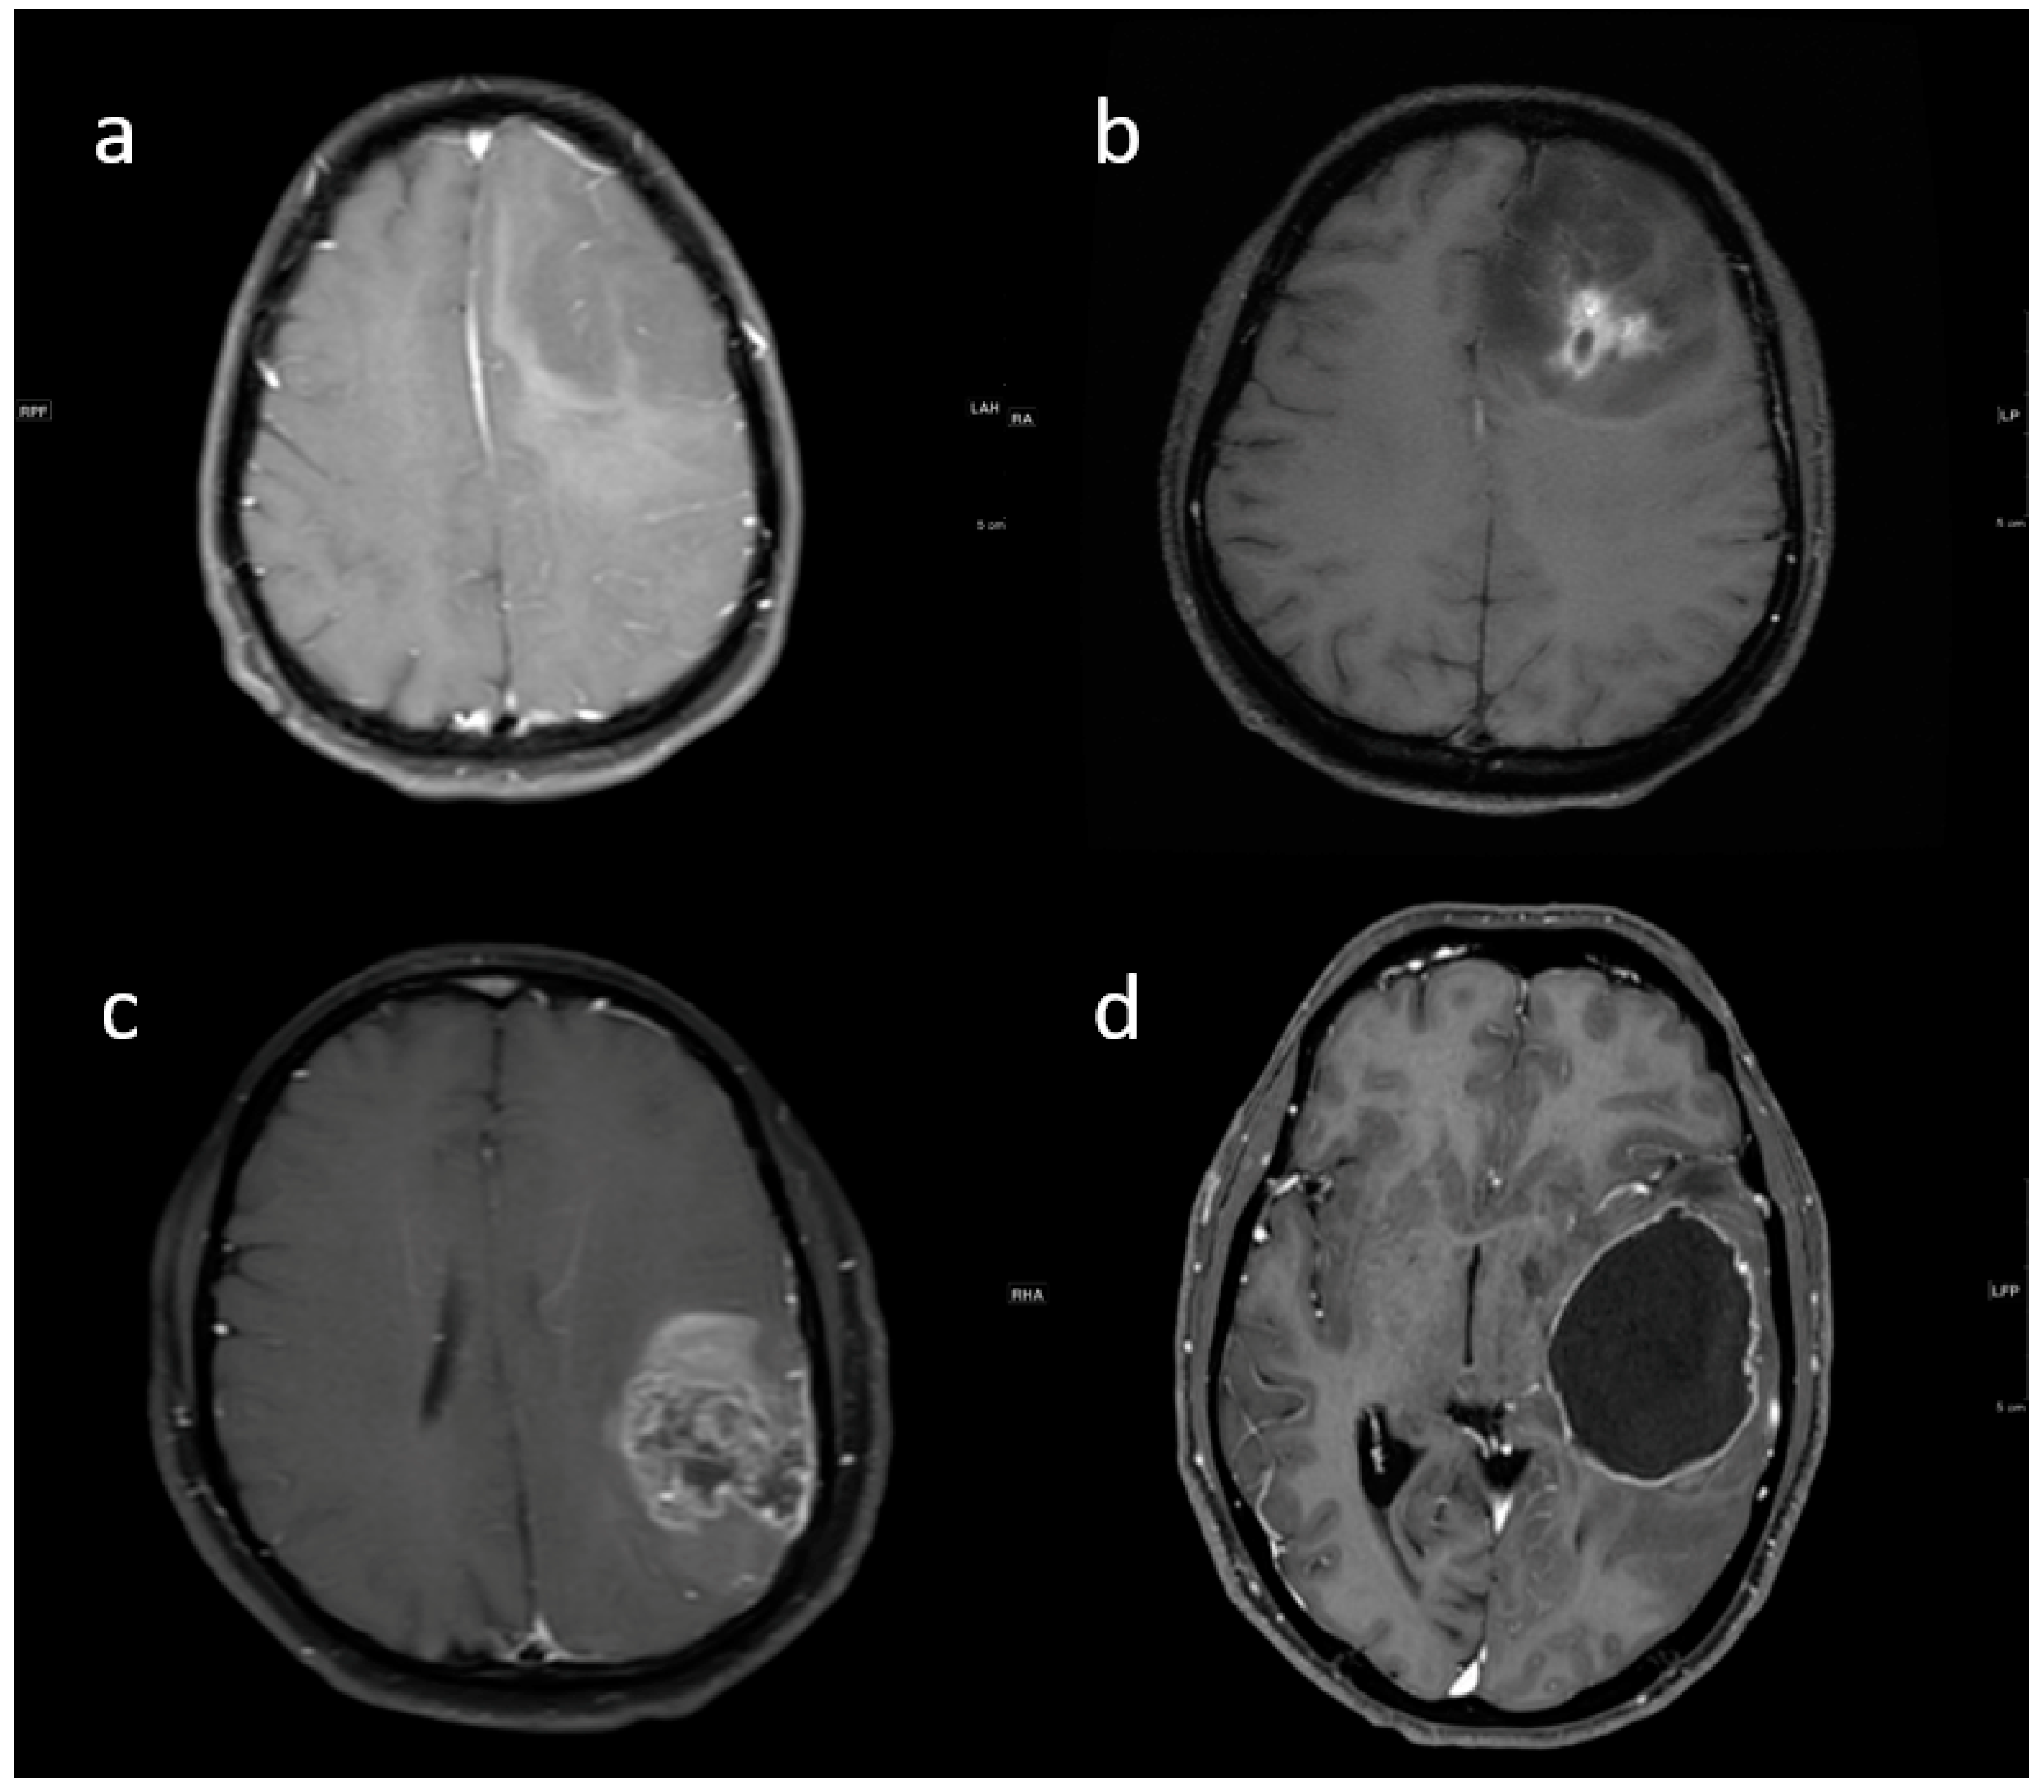

3.2. MRI Parameters of IDH-Wildtype vs. Mutant Phenotype Tumors